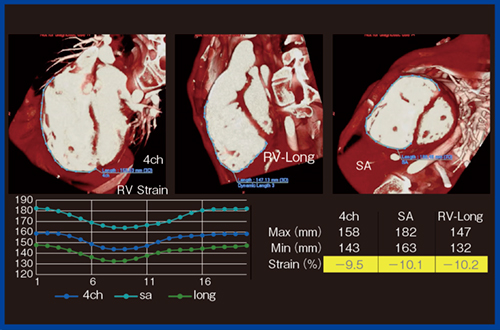

当院では,2023年からファロー四徴症に対する経皮的肺動脈弁置換術(transcatheter pulmonary valve implantation:TPVI)を行っている。ファロー四徴症は,術後遠隔期に肺動脈弁逆流が起こり,長期的に右室肥大・右室拡大を来たして不整脈や突然死に至るリスクが高まると言われている。従来は,開胸による肺動脈弁置換術(pulmonary valve replacement:PVR)が行われていたが,今後はより侵襲性の低いTPVIの普及が進むと考えられる。TAVIやTPVIなど人工弁置換術のより安全な施行のためには,術前の正確な解剖学的情報の取得が必要であり,4D-CTは必須の検査となる。4D-CTは解剖学的情報に加えて機能情報の提供が可能であり,さらに4チャンバービュー,右室長軸像(RV-Long),短軸像(SA)といった複数の断面でストレイン解析が可能になる(図8)。

TPVIに使用する人工弁(Harmony)は,肺高血圧症や肺動脈弁狭窄が強い患者には使えないなどの使用制限がある。われわれはCTストレイン解析を用いて,術前に2D-CTで肺高血圧症の推測が可能かどうかの検討を行った。肺高血圧症の有無で4チャンバービューのストレインを比較したところ,肺高血圧症がある症例では右室の動きが悪くなっていることが定量的に評価できた。42名の検討では,肺高血圧症の有無で有意な差が認められた。特に,4チャンバービューのストレインを右室流出路(RVOT)の心筋ボリュームで補正したところ,非常に高い相関が認められ,ストレイン解析によって非侵襲的に肺高血圧症を診断できると考えられる5)。

図8 TPVIのための4D-CT解析